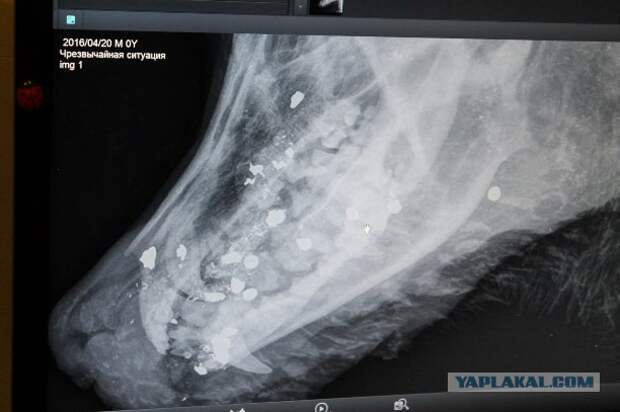

| Собаке выбили зубы, разбили нос и выстрелили в голову из ружья. Во время обследования у пса была обнаружена ружейная дробь в челюсти, черепе и позвонках. Сейчас Гром ждёт операции и находится под наблюдением врачей. | |

| | — В собаку стреляли дробью (не пневматика), а из натурального ружья. На снимках видно белые точки — это дробь. Грома будут оперировать, у него выбиты клык и несколько зубов, будут частично вытаскивать дробь, т.к. дробинки присутствуют ещё и в шейных позвонках, —рассказала волонтёр группы помощи бездомным животным «Добрые руки» Ирина Асташова. |